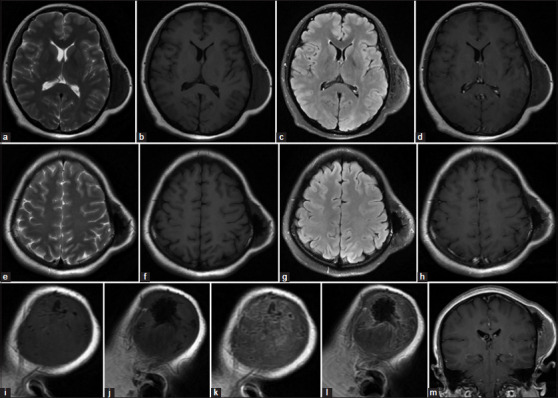

结缔组织增生纤维瘤(DF)是一种罕见的良性骨肿瘤,通常累及面部骨骼,累及颅脑极为罕见。我们报告一个独特的病例DF在一个28岁的妇女的顶骨,值得注意的是其在怀孕期间快速增长的现象,以前没有记录。该病例的影像学特征也与以往报道的所有病例不同。患者接受手术切除,组织病理学证实DF(胶原纤维瘤)的诊断。随访17个月,未见局部复发。我们也提供了32例涉及颅脑DF的病例,分析临床特征、影像学表现、治疗方法和复发模式。本病例强调了在颅脑病变鉴别诊断中考虑DF的重要性,特别是在肿瘤快速生长的孕妇中。为了减少复发的风险,广泛的手术切除仍然是推荐的治疗方法。

Desmoplastic fibroma (DF) is an uncommon benign bone tumor that typically affects the facial bones, with cerebral cranium involvement being extremely rare. We report a unique case of DF in the parietal bone of a 28-year-old woman, notable for its rapid growth during pregnancy-a phenomenon not previously documented. The imaging features of this case also differ from all but one previously reported case. The patient underwent surgical removal, and histopathology confirmed the diagnosis of DF (collagenous fibroma). After 17 months of follow-up, no local recurrence was observed. We also provide a comprehensive review of 32 cases involving DF of the cerebral cranium, analyzing clinical features, imaging findings, treatment methods, and recurrence patterns. This case highlights the importance of considering DF in the differential diagnosis of cranial lesions, particularly in pregnant patients with rapid tumor growth. Complete surgical resection with a wide margin remains the recommended treatment to minimize recurrence risk.